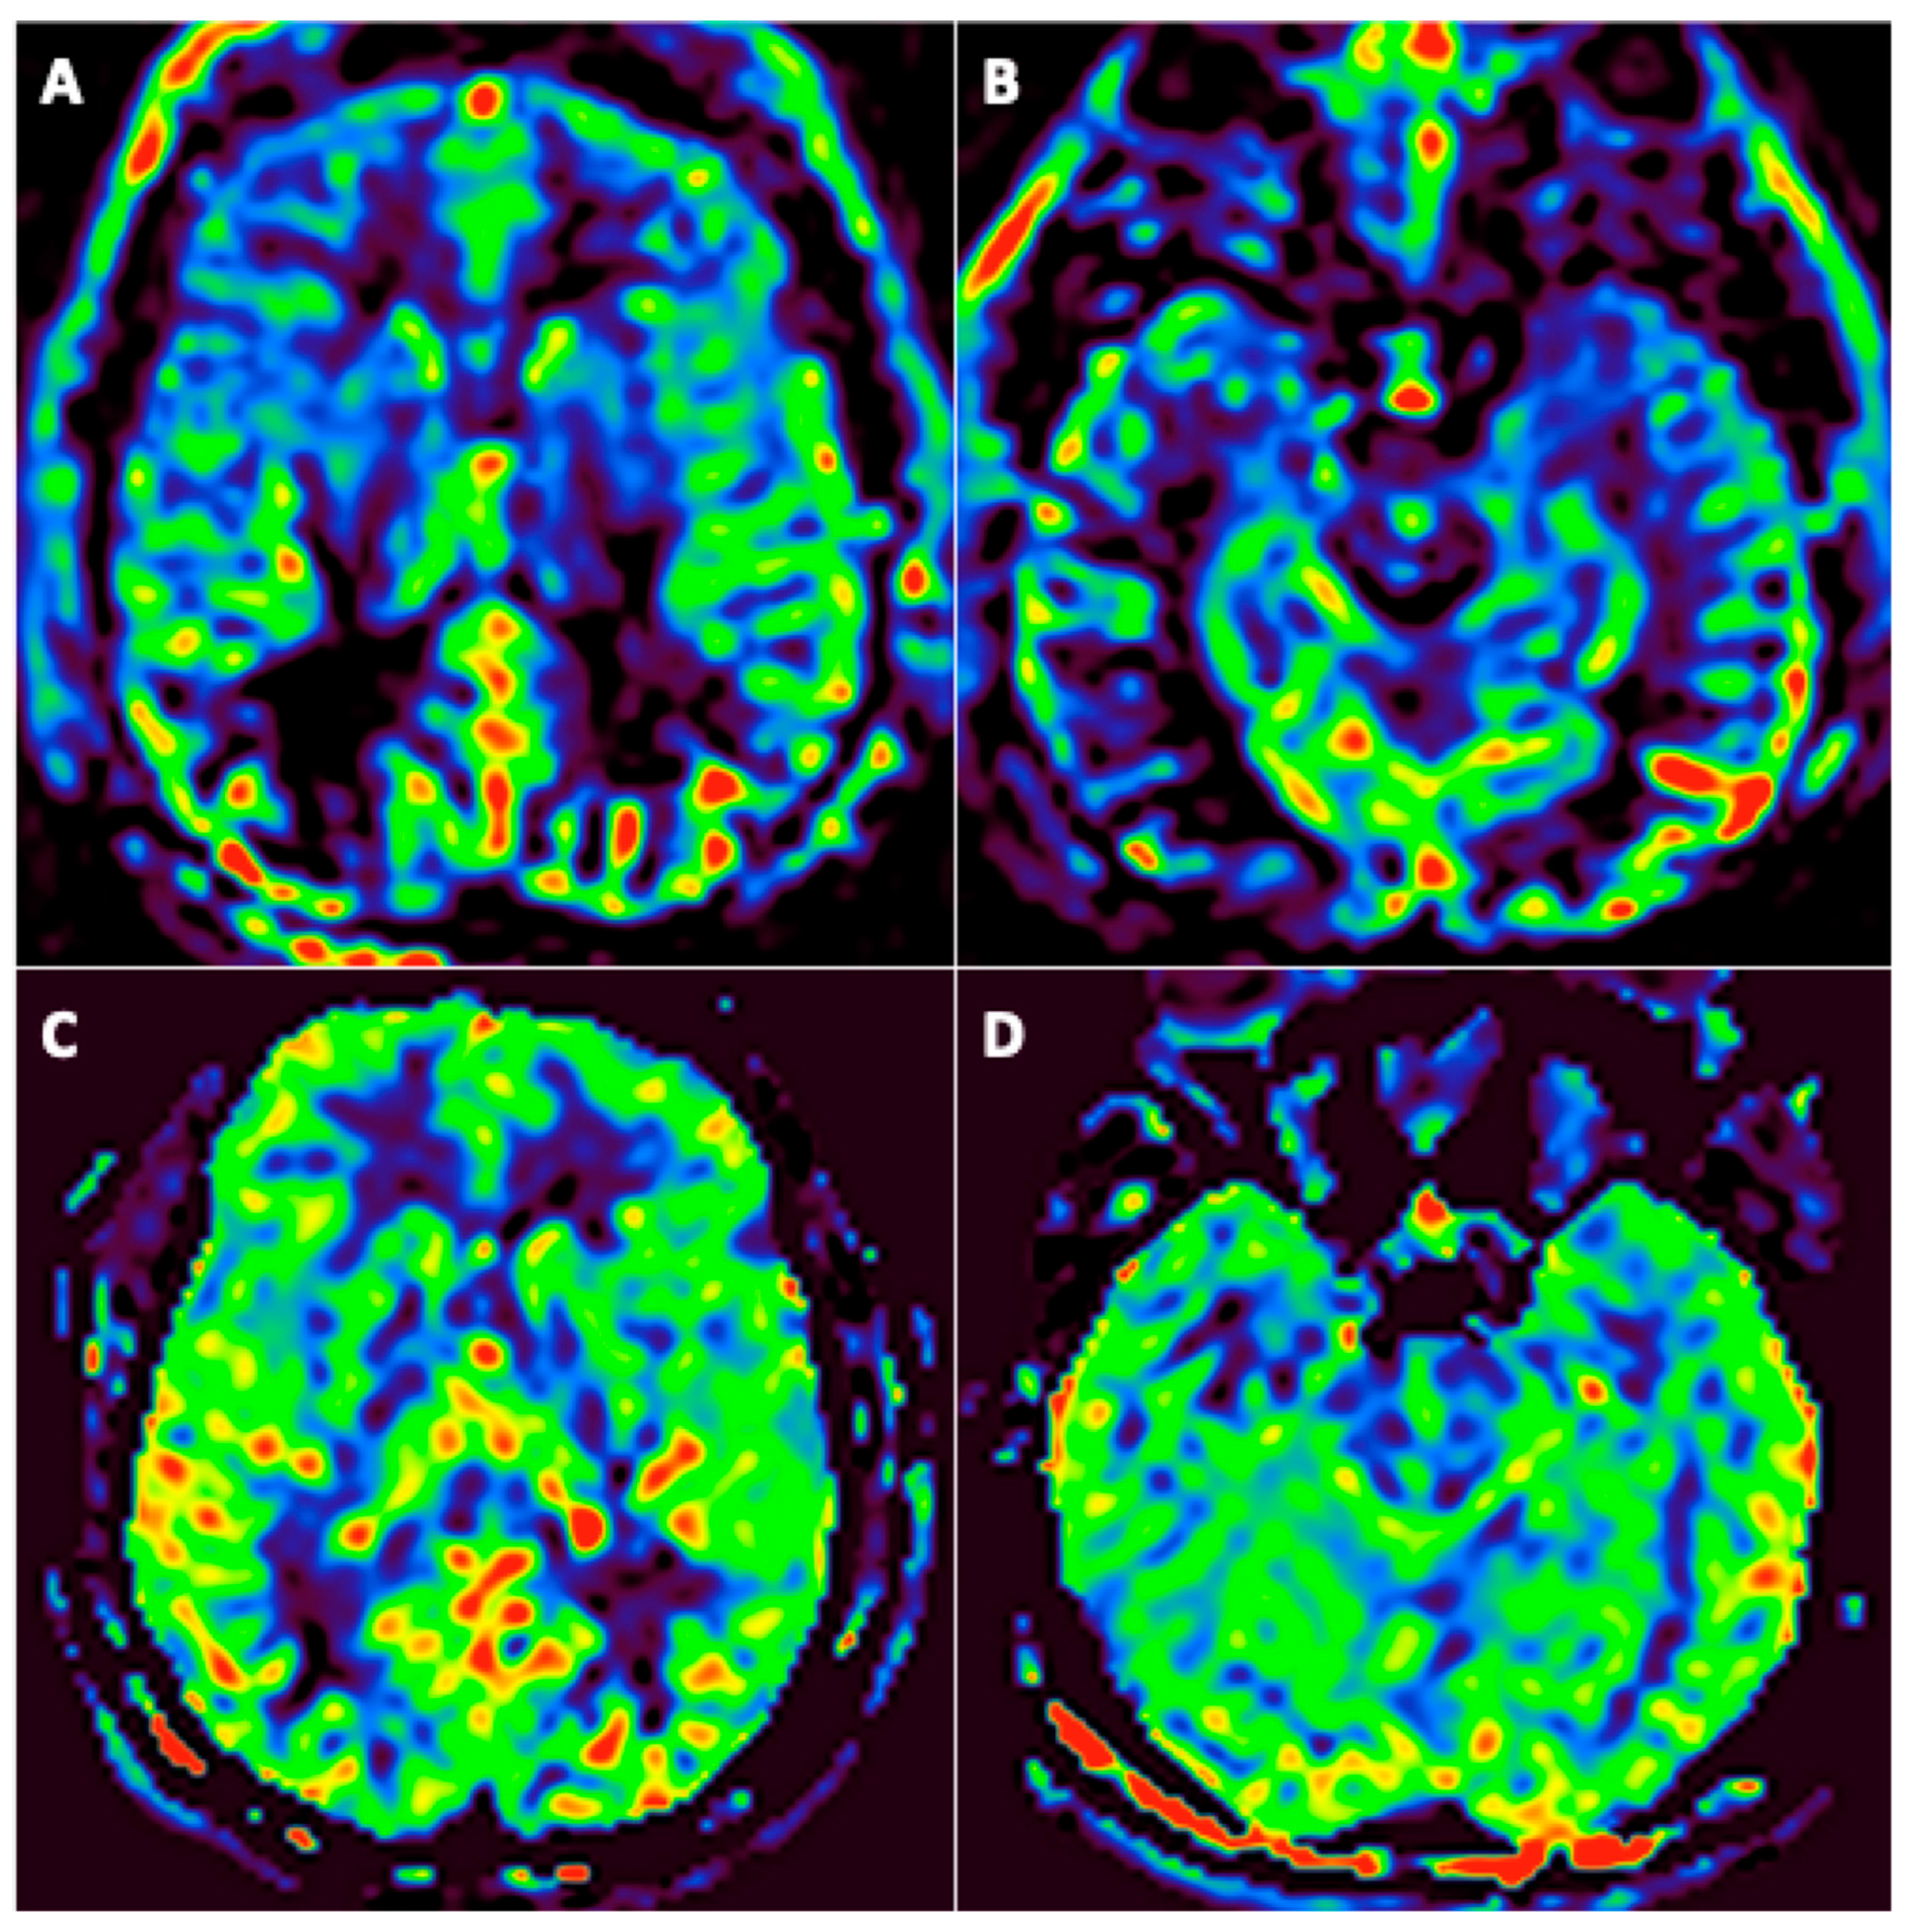

Among the 31 patients, 24 underwent at least two assessable arterial spin labeling (ASL) brain perfusion imaging at different timepoints, none of them with an intracranial arterial occlusion on MR-angiography. Among these 24 patients, 19 (79%) had abnormal brain perfusion on the initial imaging: 16 (66.7%) patients had hypoperfusion (Figure 4) and 4 (17%) had hyperperfusion. Among these 19 patients, brain perfusion had normalized in 11 (58%) of them by the last imaging session; 1 (5%) still had hyperperfusion; 1 (5%) with initial hyperperfusion had hypoperfusion in the last imaging session; and 6 (37%) patients still had hypoperfusion in the last imaging session. A qualitative improvement in brain perfusion was nevertheless present in 5 (83%) of these 6 patients. Overall, 16 (84%) patients showed at least partial normalization of their brain perfusion.

Figure 4.

A 46-year-old man (#6) initially hospitalized in the ICU (A,B), who underwent a second MRI during follow-up 92 days later (C,D). Axial arterial spin labeling (ASL) brain perfusion imaging (A–D). Abnormal brain perfusion on initial imaging with frontotemporal hypoperfusion (A,B) and normalization during follow-up (C,D).